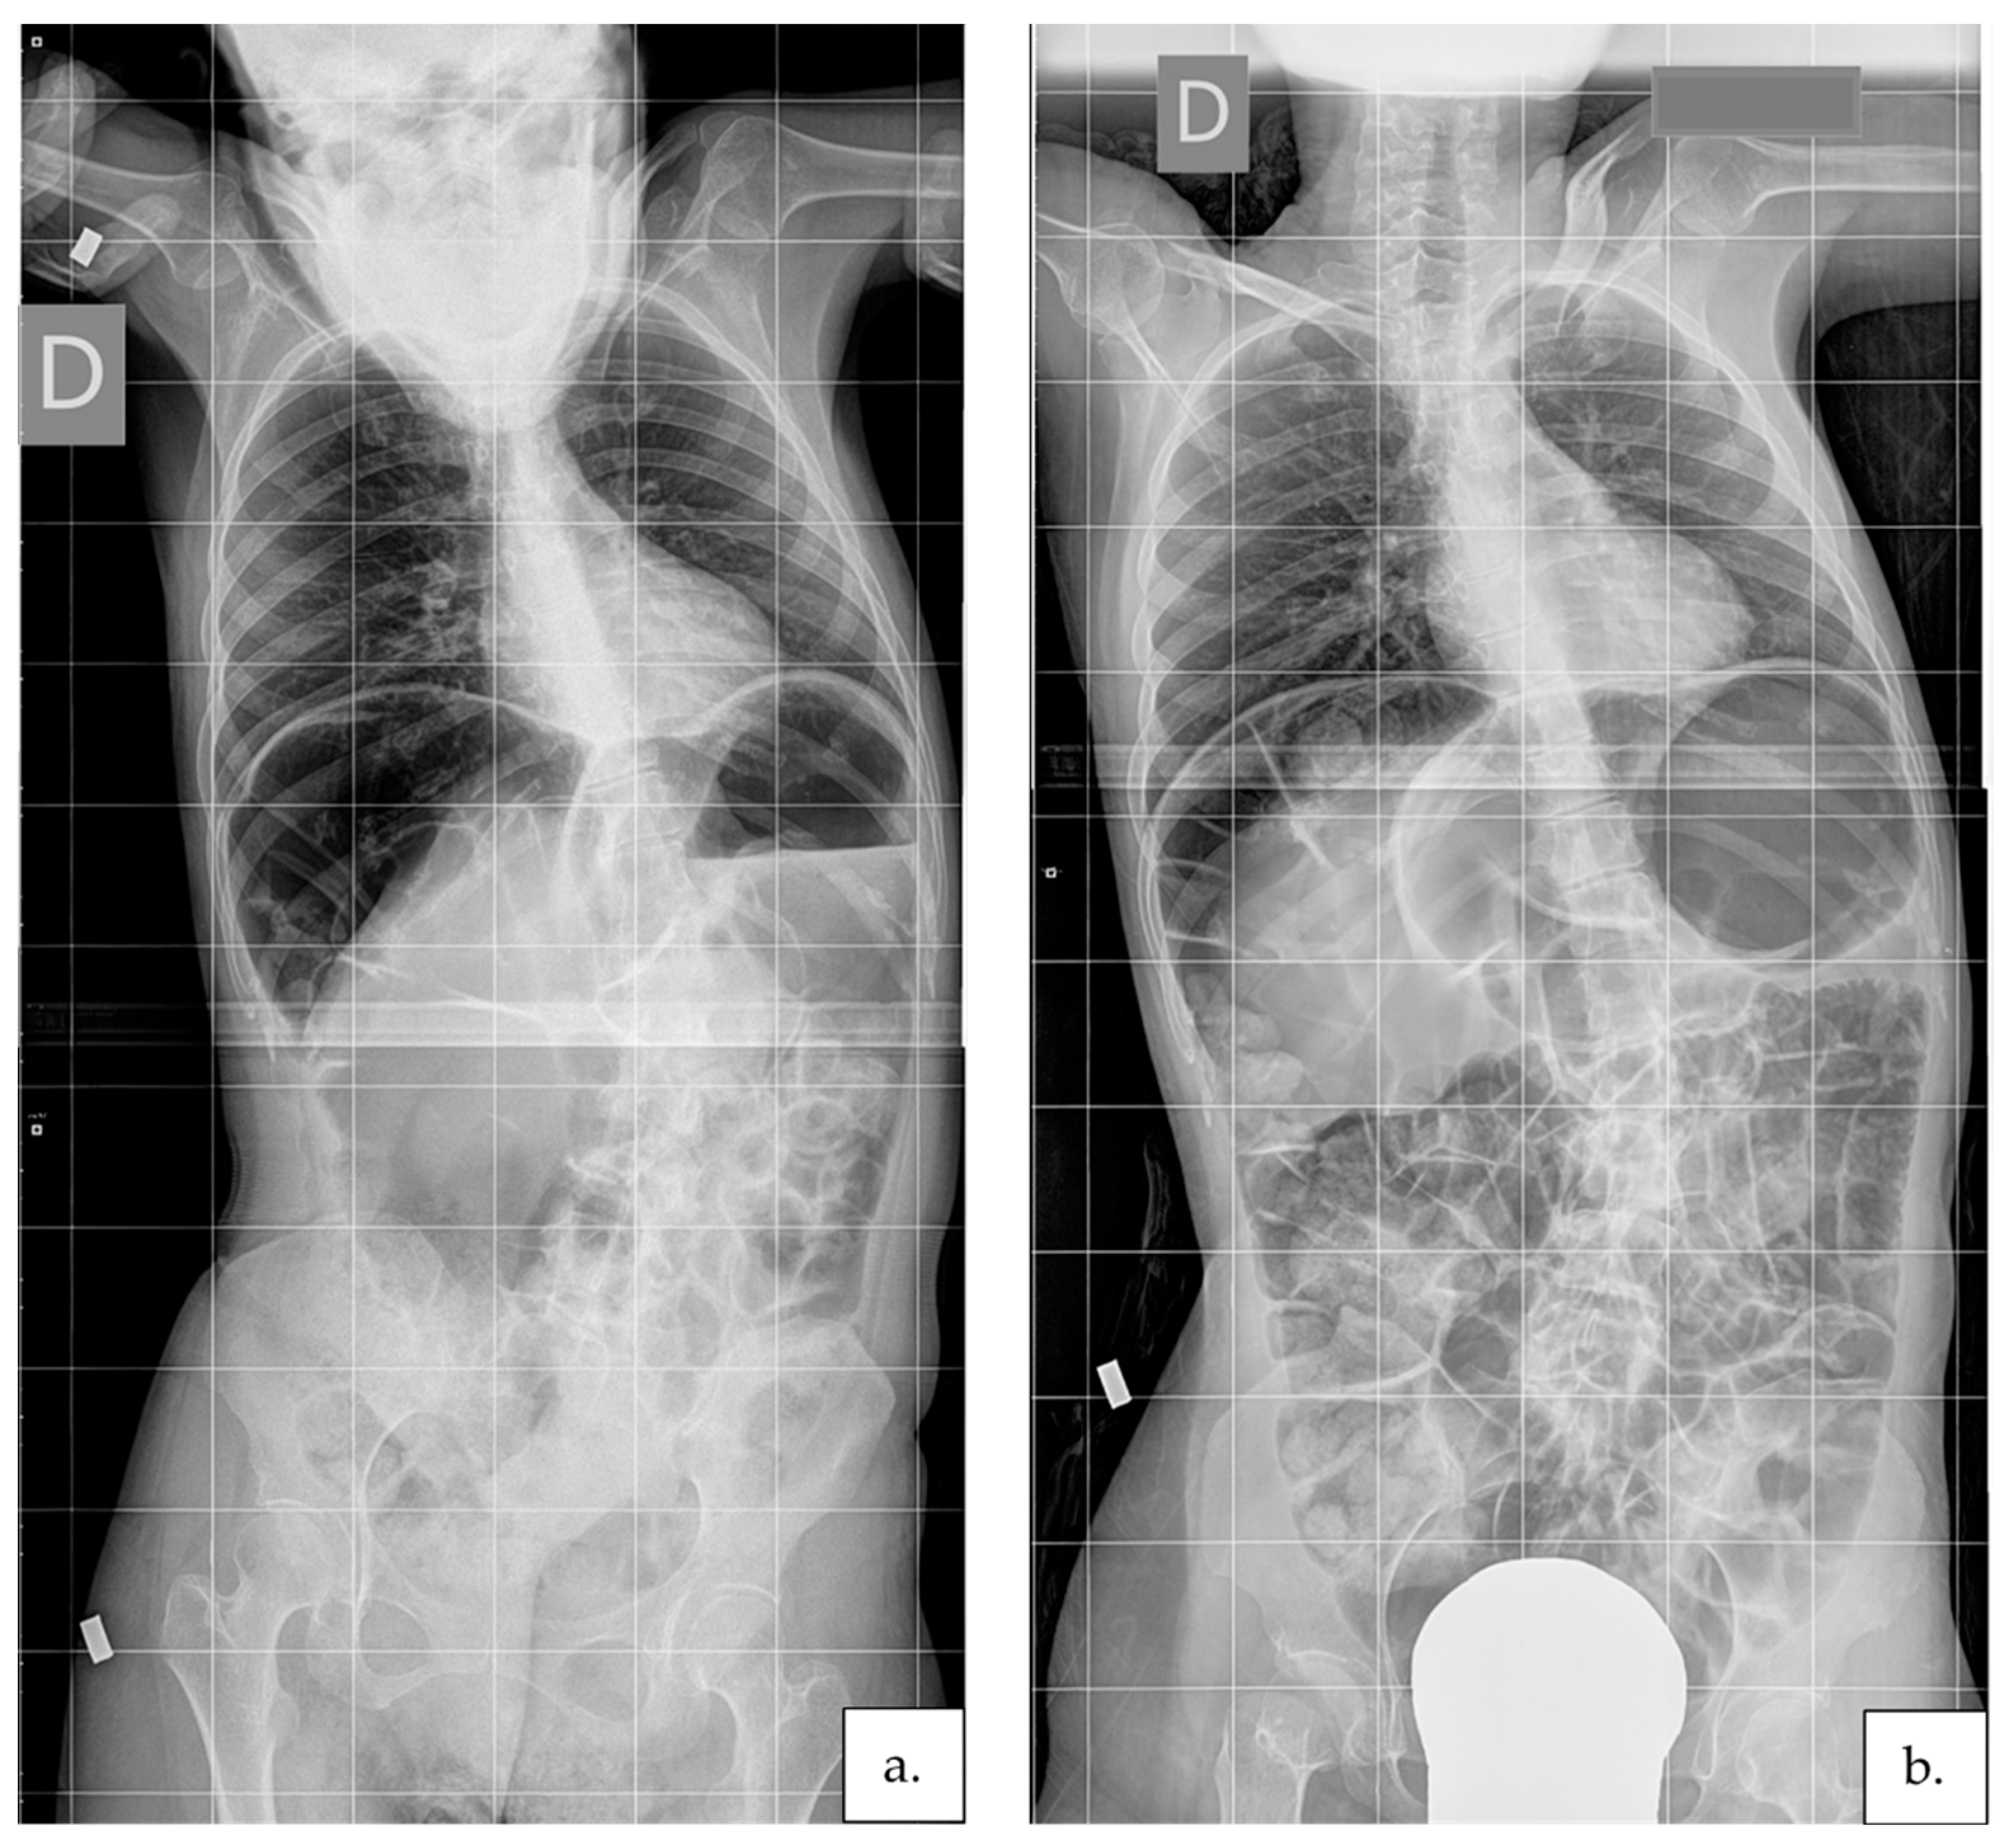

2.3.4. Scoliosis Severity

- Horng, M.-H.; Kuok, C.-P.; Fu, M.-J.; Lin, C.-J.; Sun, Y.-N. Cobb angle measurement of spine from X-ray images using convolutional neural network. Comput. Math. Methods Med. 2019, 2019, 6357171. [Google Scholar] [CrossRef] [Green Version]